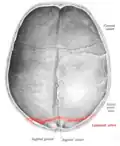

The lambdoid suture, or lambdoidal suture, is a dense, fibrous connective tissue joint on the posterior aspect of the skull that connects the parietal bones with the occipital bone. It is continuous with the occipitomastoid suture.

The lambdoid suture is between the paired parietal bones and the occipital bone of the skull. It runs from the asterion on each side.

The lambdoid suture is named due to its uppercase lambda-like shape.

Lambdoid suture seen from above. -